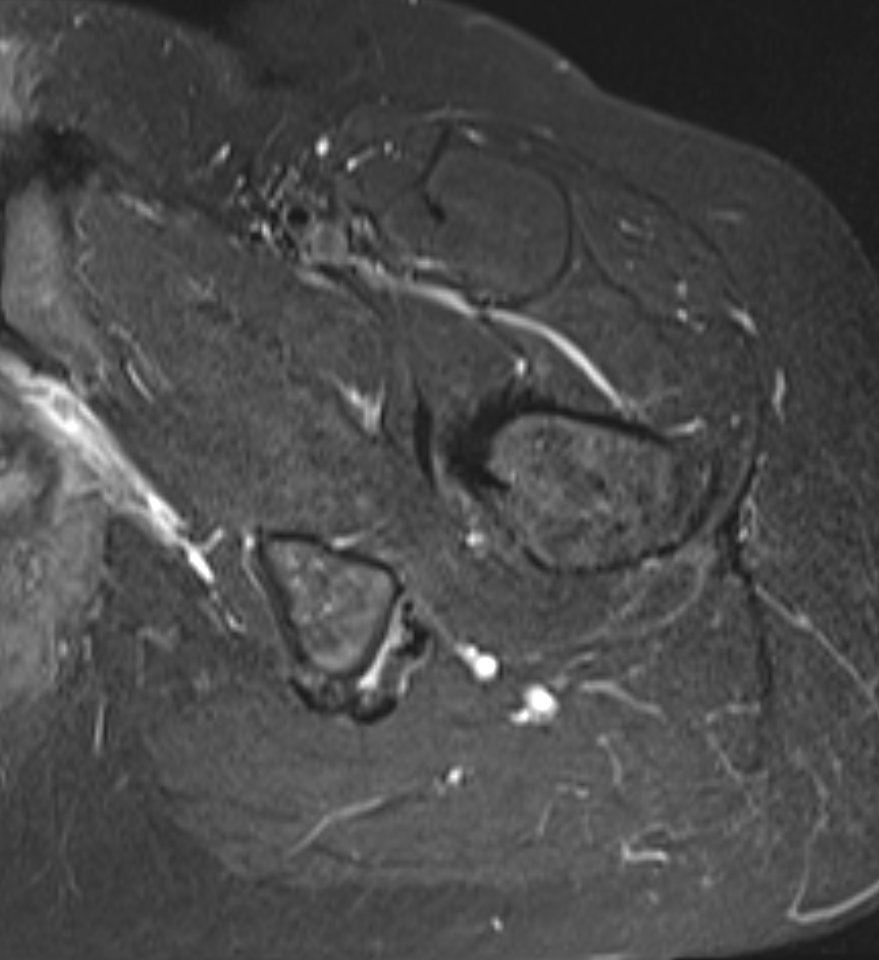

Approach to proximal hamstring

- identify hamstring muscle belly and conjoint tendon

- sciatic nerve lateral to conjoint

- semimembranosus anterior and medial to conjoint

- release semimembranosus tendon near insertion

- suture to conjoint tendon

Identify sciatic nerve lateral and semimembranosus tendon medial to conjoint muscle belly and tendon

Divide semimembranosus tendon and suture to conjoint tendon (star - sciatic nerve, # - conjoint tendon)